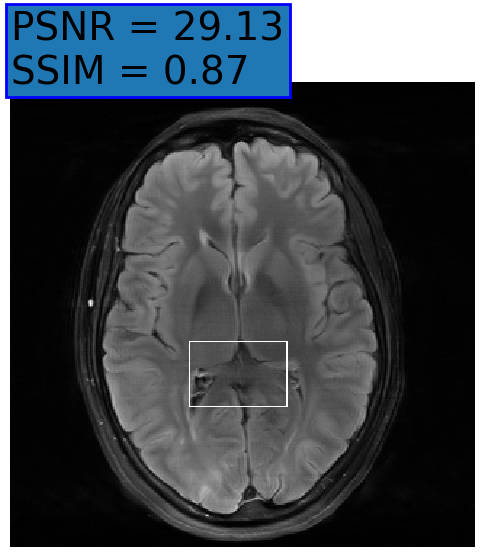

Figure 3: Reconstructions results. Rows 1 and 3: Examples of comparing the ground truth (GT) fully sampled image to the reconstructed images obtained by the three models (1-3), NPB-REC, baseline, E2E-VarNet trained with Dropout, and the NPB-REC std. map at accelerations R=4𝑅4R=4, R=8𝑅8R=8, respectively. Rows 2 and 4: The corresponding annotated ROIS of Nonspecific white matter lesions.

Fig. 3 presents examples of reconstruction results obtained by (1) our NPB-REC approach, (2) the baseline, and (3) Monte Carlo Dropout, for equispaced masks with two different acceleration rates R=4𝑅4R=4 and R=8𝑅8R=8. The reconstructed images predicted by the three models are smoother than the reference image. This is due to the fact that all the models were trained with SSIM loss, which tends to produce overly smooth reconstructions while preserving the diagnostic content and the anatomical features Sriram et al. (2020a). These images can be enhanced by dithering the image by adding a small amount of random Gaussian noise to produce a more textured reconstruction, as proposed in Sriram et al. (2020b).

Table 1 presents the mean PSNR and SSIM metrics, calculated over the whole inference set, for the three models. Our NPB-REC approach achieved significant improvements over the other methods in terms of PSNR and SSIM (Wilcoxon signed-rank test, pmuch-less-than\ll1e-4, except for SSIM values in line W, R=4𝑅4R=4 where they are roughly the same for NPB-REC and Baseline). The improvement in the reconstruction performance can be noted both quantitatively from the metrics, especially for masks with acceleration rate R=8𝑅8R=8, and qualitatively via the images of annotations, where our results show less smoothness than those obtained by Dropout.